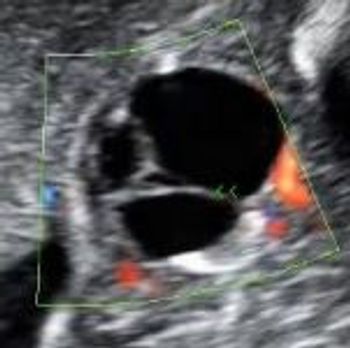

QUIZ: These images reveal a specific structure of the fetal eye. Can you identify it?